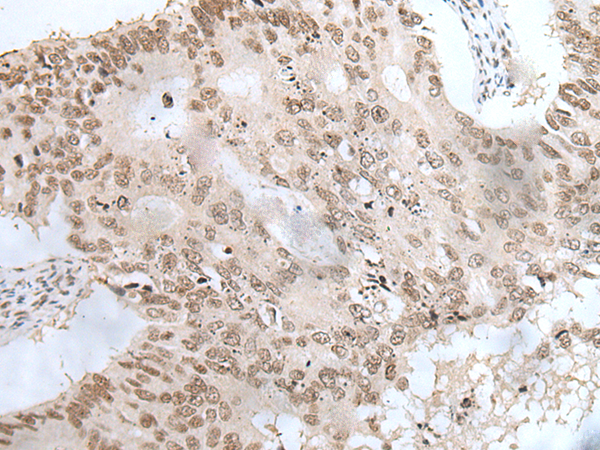

IHC positive control:

Human colorectal cancer and human ovarian cancer

IHC Recommend dilution:

20-100